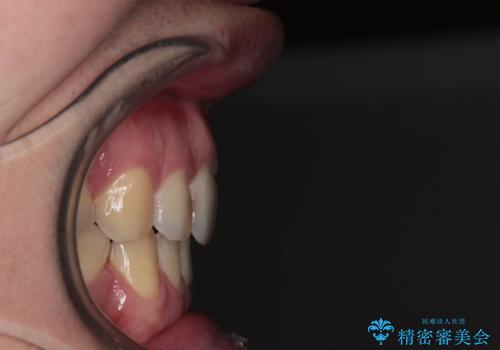

上下唇をしっかり合わせようとすると、顎先が前方に突出してしまうほど口が閉じにくい状態でした。

口元の突出感を改善するために上下左右の第一小臼歯4本を抜歯し、ワイヤー装置にて矯正治療を行うこととしました。